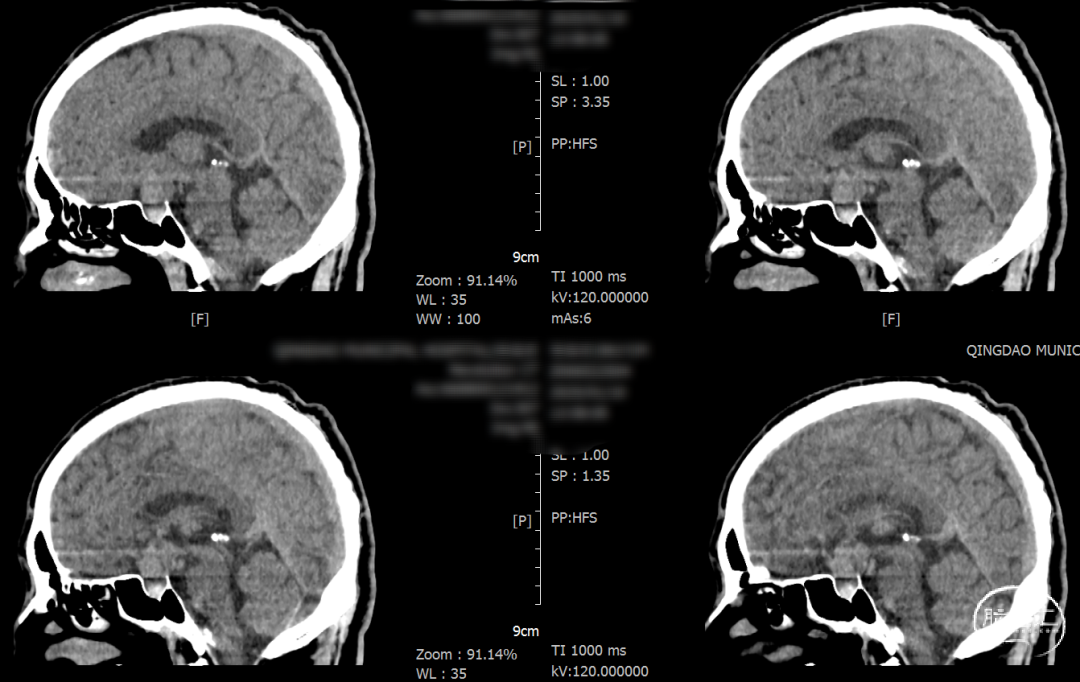

术后一天检查。